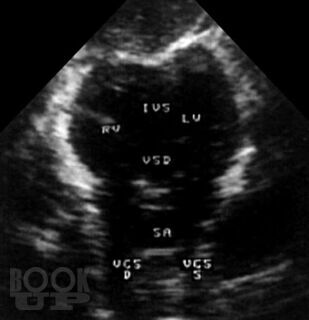

В атласе на большом числе богато иллюстрированных примеров дана эхо- и допплеркардиографическая картина врожденных пороков и ряда заболеваний сердца, а также правила применения методики ультразвукового исследования. Издание восполняет дефицит информации об ультразвуковой диагностике многих сложных врожденных пороков сердца и возможности оценки состояния больных после хирургической коррекции порока.